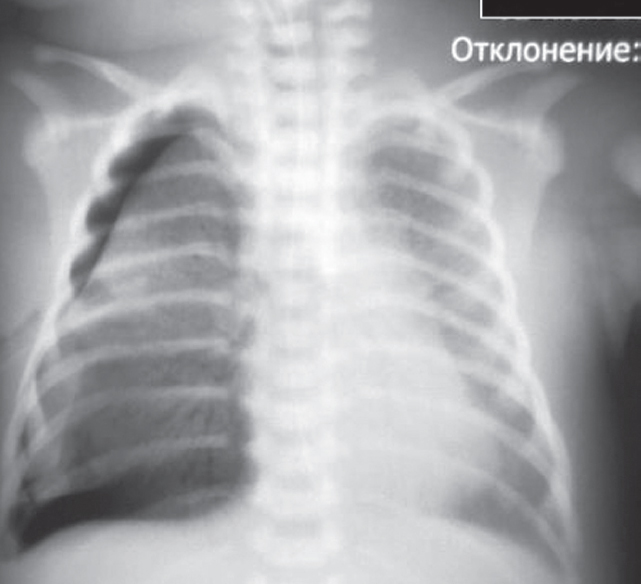

В статье представлен случай успешного лечения острого респираторного дистресс-синдрома у доношенного новорожденного, осложнившегося баротравмой легких, с применением монобронхиального введения экзогенного сурфактанта под рентгенологическим контролем. С целью оценки течения заболевания и эффективности лечения проведен ретроспективный анализ медицинской документации. С первых минут жизни у ребенка отмечались дыхательные расстройства, что стало основанием для проведения неинвазивной искусственной вентиляции легких. В динамике выявлено прогрессирование гиперкапнии и гипоксемии, в связи с чем была выполнена интубация трахеи и начата конвекциональная искусственная вентиляция легких с FiO2 = 1,0. Ключевой элемент терапии, позволивший достичь стабилизации состояния и регрессирования нарушений газообмена с полным выздоровлением пациента, — монобронхиальное введение экзогенного сурфактанта.

Монобронхиальное введение сурфактанта при остром респираторном дистресс-синдроме с гетерогенным поражением легких является эффективным вариантом лечения и может использоваться в клинической практике при рефрактерной гипоксемии.